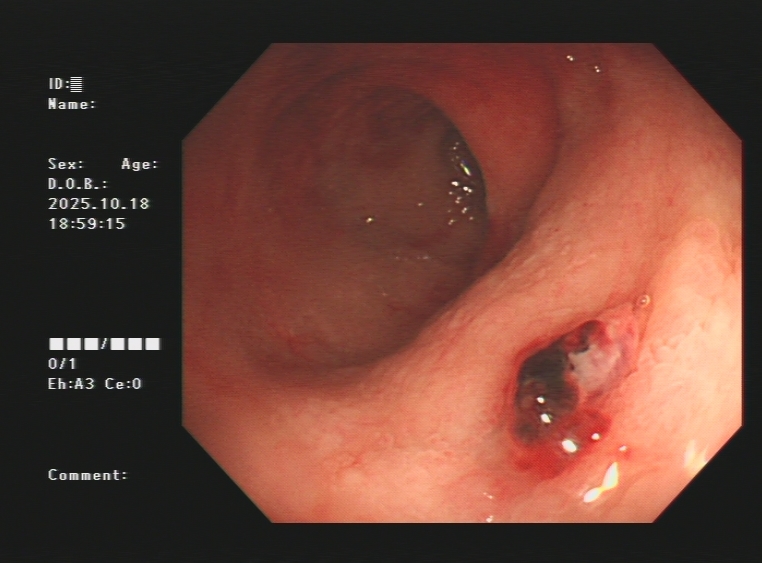

1.上消化道出血常见原因:消化性溃疡(胃溃疡、十二指肠溃疡)、食管炎、急性糜烂出血性胃炎、上消化道肿瘤(食管癌、胃癌)、剧烈呕吐造成的食管贲门黏膜撕裂伤、肝硬化引起的食管胃底静脉曲张。以下是一些常见的上消化道出血内镜图片:

急性胃黏膜病变出血、十二指肠球部溃疡出血及镜下止血夹止血